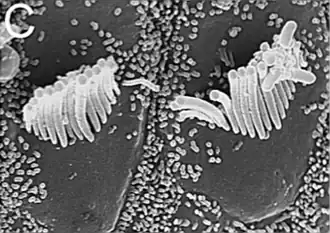

Células ciliadas dentro de la cóclea.

Células ciliadas internas y externas del Órgano de Corti. Vista de superficie apical con estereocilios.

Estereocilias de células externas del órgano de Corti.